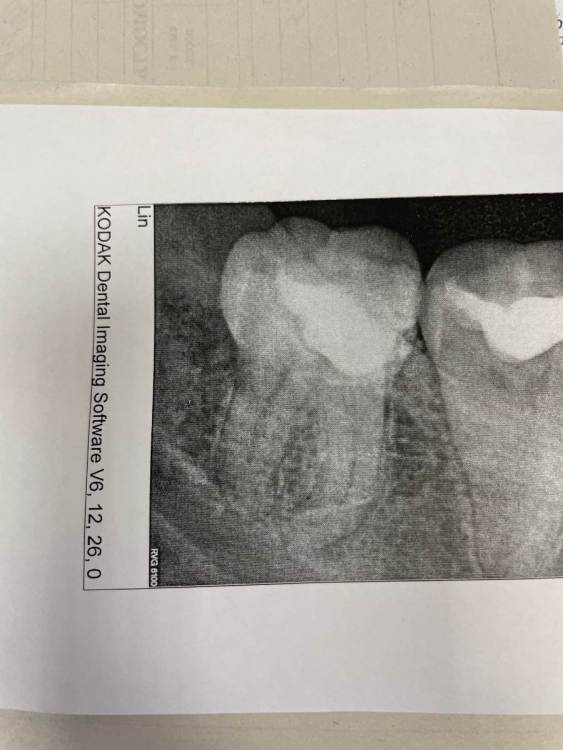

a.sataeff Опубликовано 10 июня, 2022 Поделиться Опубликовано 10 июня, 2022 (изменено) Добрый день. 35 лет. Можно ли спасти нижнюю восьмерку, разболелся, врач поставила пока лекарство. Стенки нет одной. Даже вопрос не можно, а нужно ли спасать? Изменено 10 июня, 2022 пользователем a.sataeff Ссылка на комментарий

red_butler Опубликовано 13 июня, 2022 Поделиться Опубликовано 13 июня, 2022 Здравствуйте, можно сохранить, но не рационально. Если он Вам дорог, то ищите грамотного терапевта для проведения лечения корневых каналов и востанавливайте зуб искусственной коронкой и меняйте подход к индивидуальной гигиене. А лучше прощайтесь с зубом 1 Ссылка на комментарий

red_butler Опубликовано 14 июня, 2022 Поделиться Опубликовано 14 июня, 2022 3 часа назад, a.sataeff сказал: Сходил очно в две клиники, в одной предложили штифт/пломба, в другой вкладку. в моём случае если удалять жалко, предпочтительнее коронка? Спасибо большое. Для полного понимания нужно оценить тот объем твердых тканей зуба который останется посте эндодонтического (корневых каналов) лечения, предварительно мне видится искуственная коронка. 1 Ссылка на комментарий